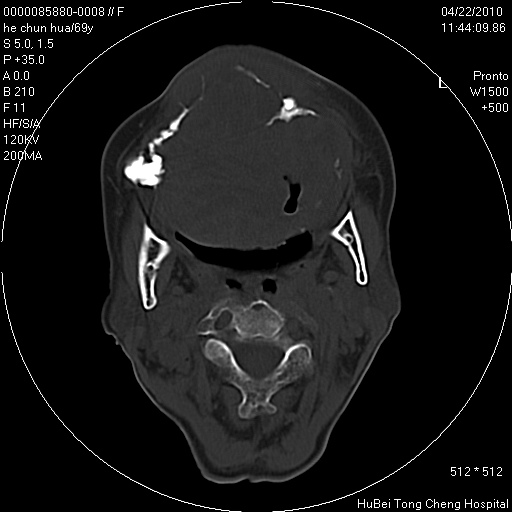

标题: CT25937:女,69Y

硬腭部包块十余年,渐进性增大。

病程长,考虑巨细胞修复性肉芽肿可能性大;

鉴别:神经源性病变、硬结病等。

五楼说得有道理,支持一下。巨细胞修复性肉芽肿好象是外伤出血后引起的修复性改变,骨质呈溶骨性破坏,但病程呈良性过程。